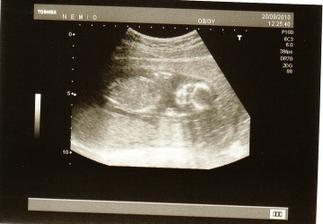

2.9. UTZ dopadl výborně. Máme 6,5cm, mimísek se poctivě ukazoval, dost v bříšku řádil. Máme všechno co máme mít, nic nechybí ani nepřebývá🙂 Další kontrola v poradně bude 30.9. a UTZ až 4.11.:( Už teď se s tatínkem těšíme, až prcka zase uvidíme;)